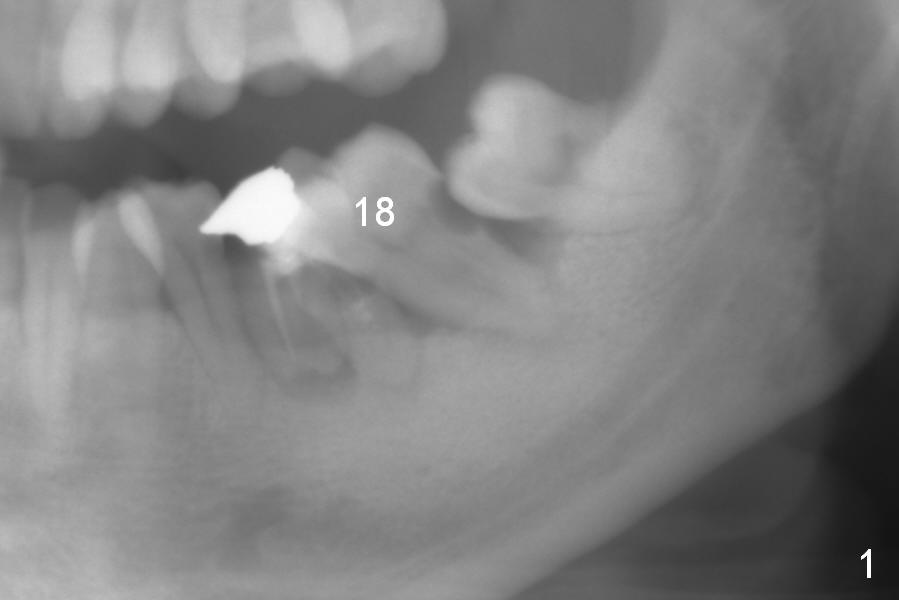

A 42-year-old woman has toothache at #18. This tooth is mesiolingually inclined with severe bone loss (Fig.1). The tooth #19 has crown fracture with poor RCT and + PARL, although asymptomatic. Due to finance, the tooth #18 will be extracted first (no Antibiotic, Fig.2 black area). During socket treatment, the mesial portion of the tooth #17 is to be trimmed (Fig.2 purple area). Osteotomy is initiated in the middle of the edentulous region (Fig.3 (red), in the mesial slope of the socket). If the primary stability of the implant is acceptable, fabricate a splinted provisional for #18 and 19 with occlusal clearance. The proximal contact with the neighboring teeth should be solid to increase retention. The provisional should cover the socket completely. Reline until satisfaction. The last resort is periodontal dressing. Impression and photos will be taken immediately preop.